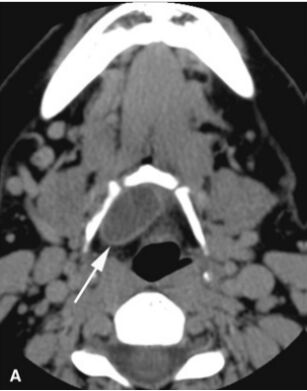

74.一位中年女性因前頸部出現不痛的腫塊而就醫,該腫塊的電腦斷層影像如白色箭頭所指,下列何者為最可能之臨床診斷? (A)branchial cleft cyst (B)lymphoepithelial cyst (C)thyroid goiter (D)thyroglossal duct cyst